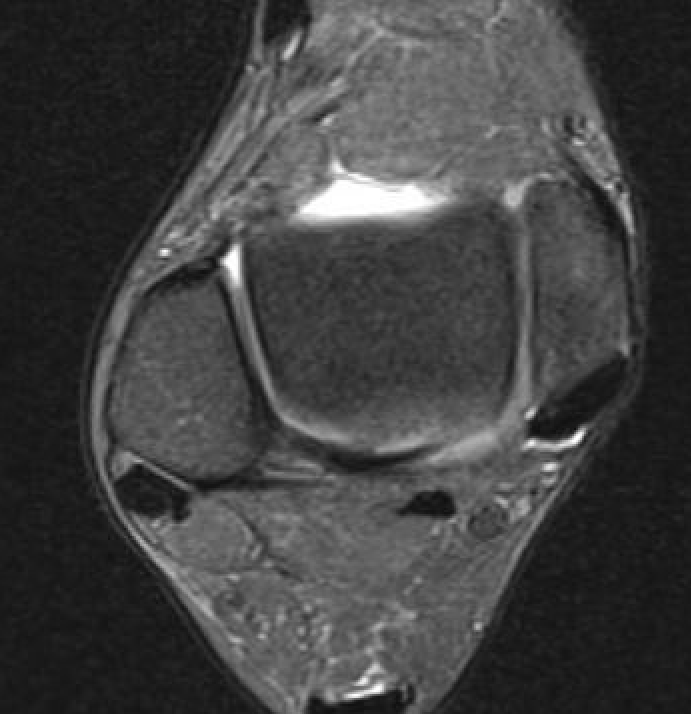

MRI

CFL tear